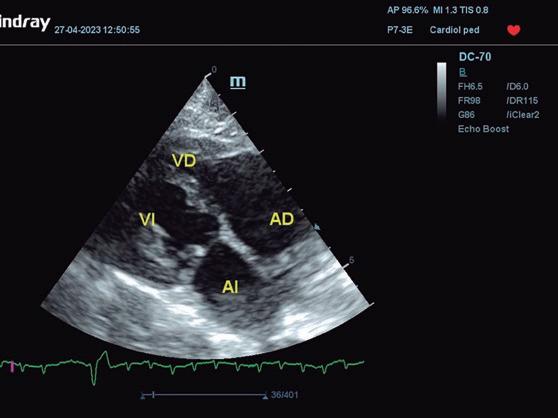

En la ecocardiografía se advierte un aumento del tamaño de cámaras cardiacas derechas (figura 4) y regurgitación tricúspide evidenciada con Doppler color. El movimiento de la pared libre del ventrículo derecho puede estar reducido en algunos gatos, mientras que el del septo interventricular puede ser paradójico. La cavidad del ventrículo izquierdo puede ser normal o estar disminuida, aunque la aurícula izquierda puede estar aumentada en algunos gatos.3

• Modo B: en la proyección paraesternal derecha eje largo, se observó un jet de regurgitación mitral con dirección posterior y SAM (figura 3). En el eje corto derecho a la altura de la base cardiaca se observó un ratio atrio izquierdo/aorta (AI/Ao) de 1,92 (>1,6 se considera dilatación AI) (figura 4). Además, se observó hipertrofia de la pared del septo interventricular (SIV) de 7,6 mm y la pared libre del ventrículo izquierdo (PLVI) la 8,4 mm (hipertrofia >6 mm) (figura 5).

Cardiomiopatía restrictiva (RCM)

Se caracteriza por la presencia de disfunción diastólica, sin engrosamiento de las paredes del miocardio1, y representa un 15-20 % de todas las cardiomiopatías felinas.2

El diagnóstico definitivo de la CMR requiere la identificación ecocardiográfica de disfunción diastólica en ausencia de cardiomiopatía hipertrófica; se observa un patrón anómalo de llenado de VI o incluso llenado restrictivo en estadios más avanzados de la enfermedad.2,3

Aunque los hallazgos no están uniformemente aceptados2,3,5, se observa dilatación del atrio izquierdo (con posible regurgitación mitral leve), o de ambos atrios; a nivel